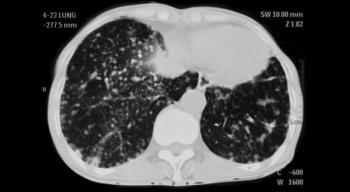

While the incidence of irAEs is relatively low, the absolute number of patients receiving immune checkpoint inhibitors is steadily increasing. Thus, it is likely that, with time, larger numbers of patients will develop irAEs, including pneumonitis.